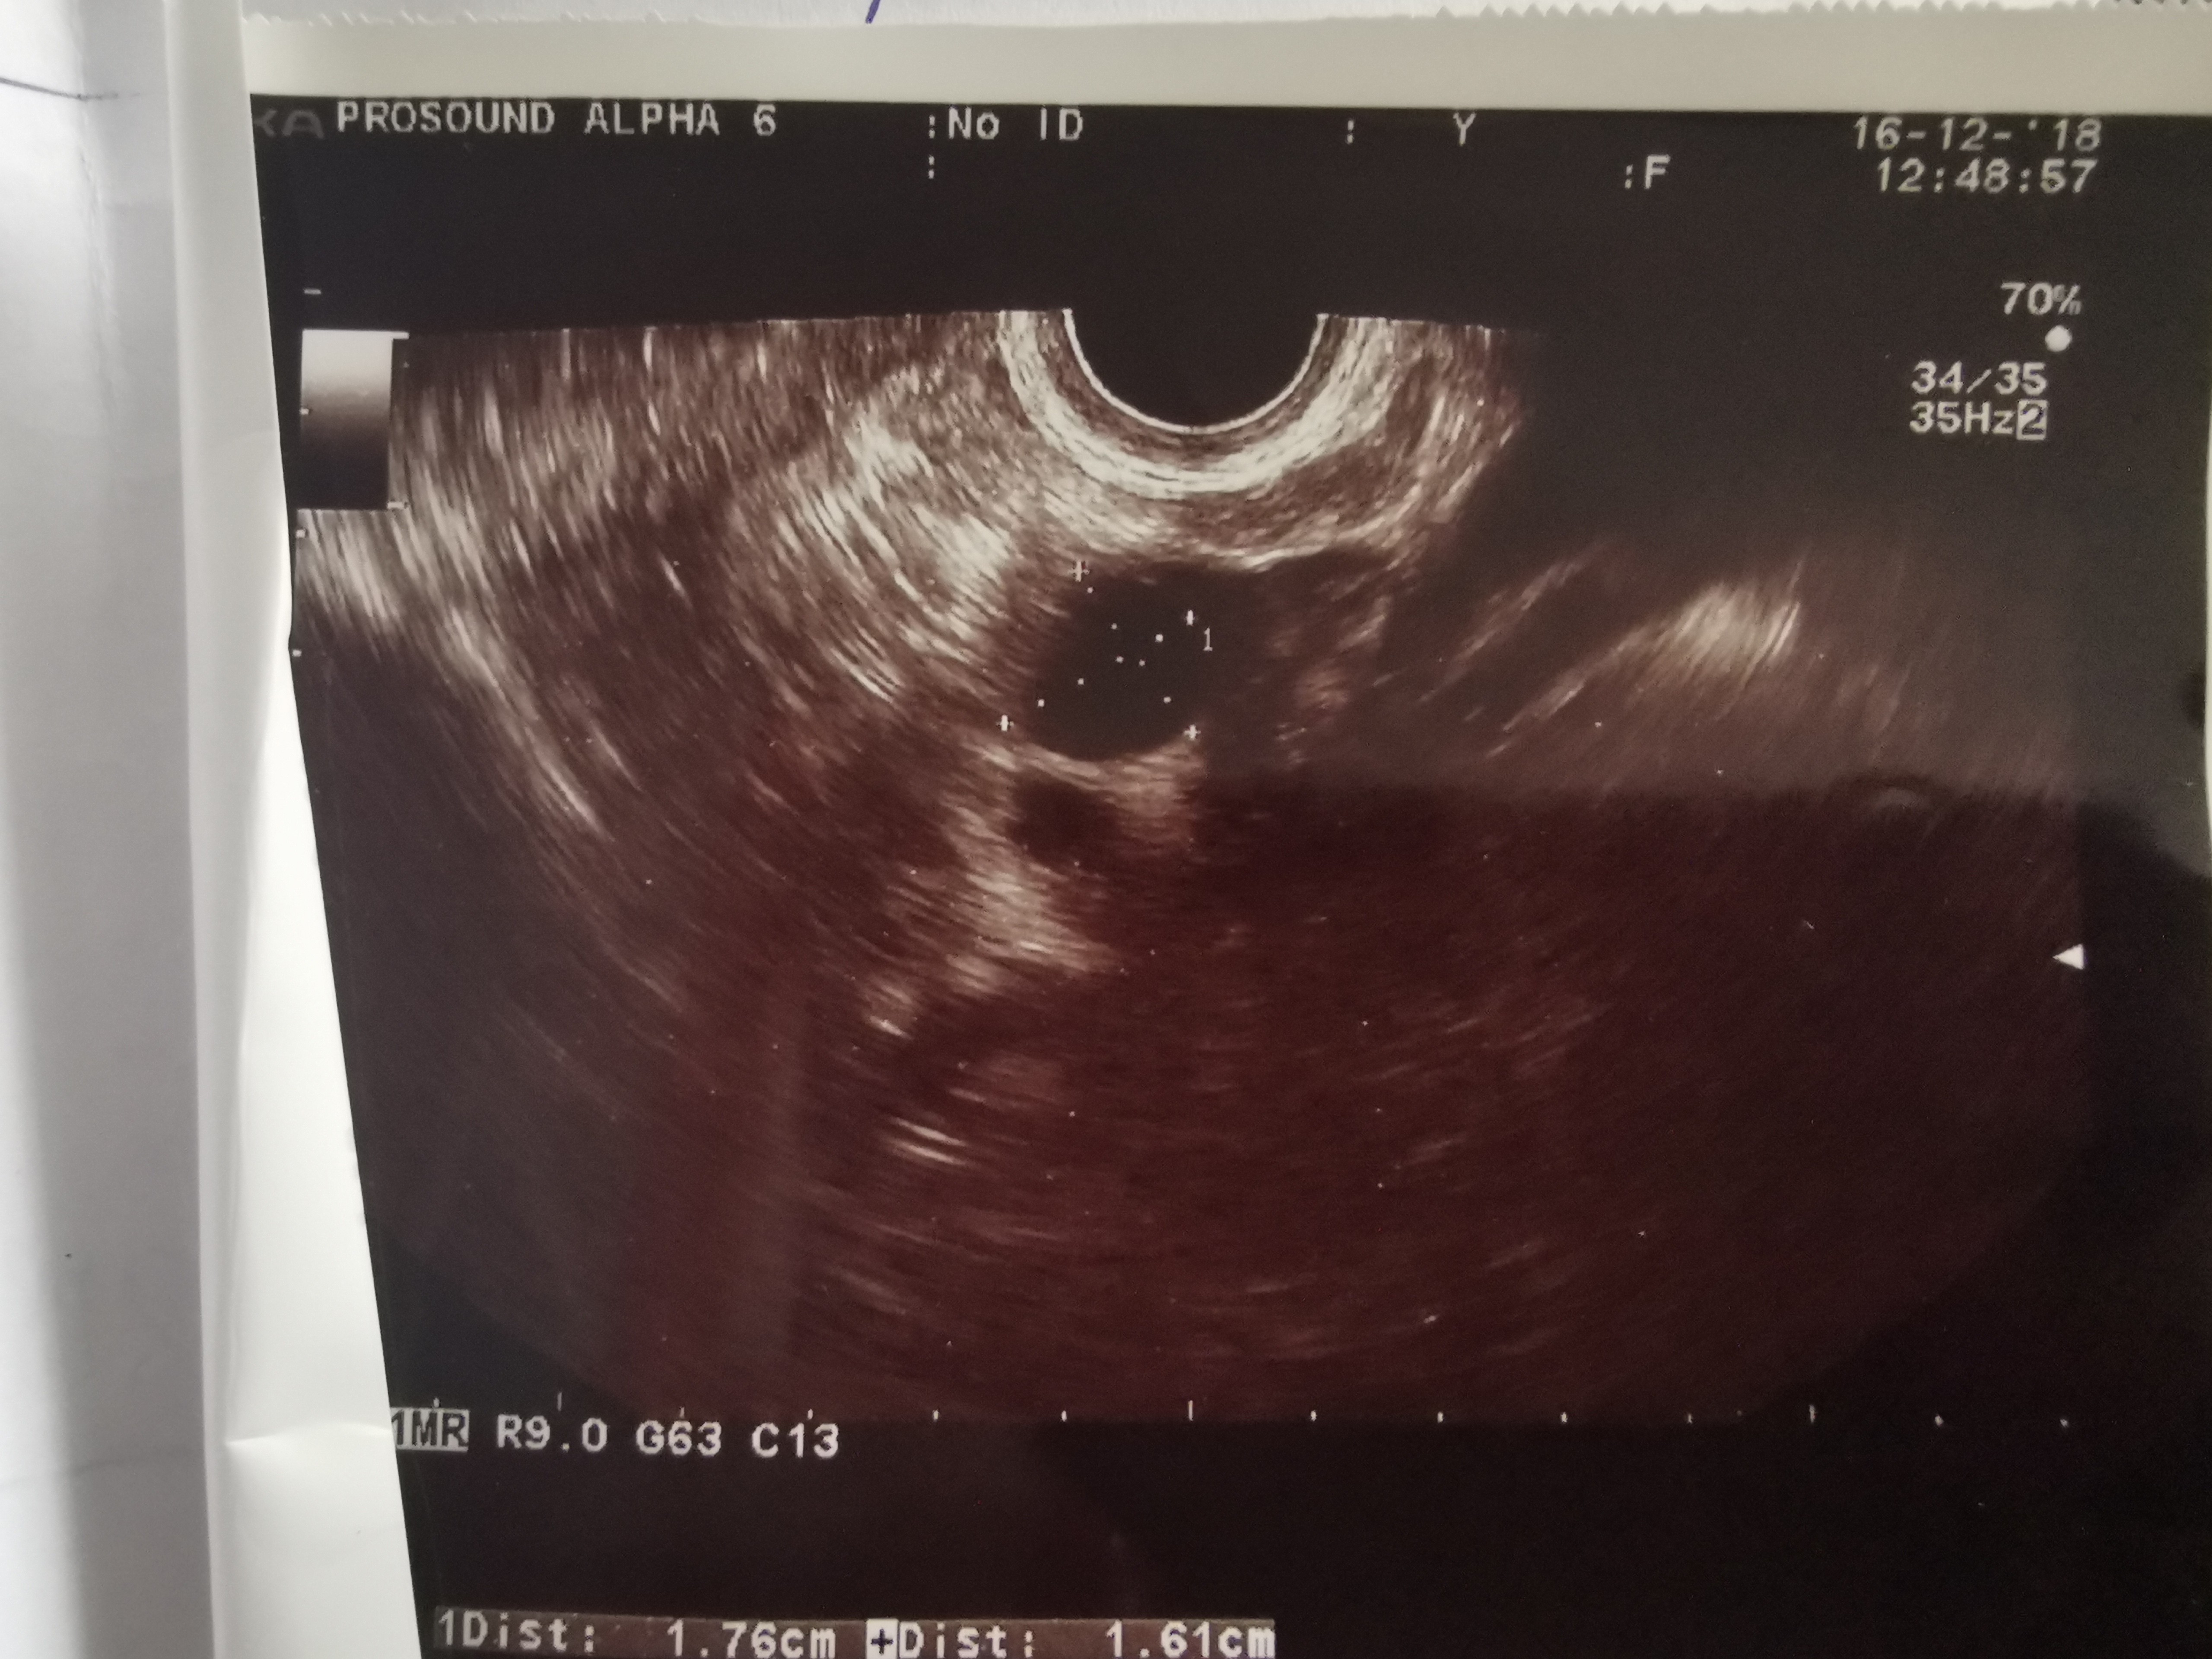

Ja widzę [emoji7][emoji7] kiedyś jakaś laseczka z tego forum pokazała zdjęcie pęcherzyka i od razu jak mi robił usg zobaczyłam. Dziś też zanim mi gin powiedział, że pękł widziałam że go nie ma i jest tak zamazane.

Haha to chyba mój pęcherzyk był [emoji23][emoji23]

Ej bo teraz mnie to nurtuje. Lekarz nic nie mówił, a ja nie pytałam. Jak byłam na wczesnej ciazy, zrobił zdjecie zarodka, ale był tam pęcherzyk, tzw. Osobny. Kto to wyjaśni? Może miały być 2 ale coś poszło nie tak i lekarz dlatego nic nie wspominał, bo pewnie to się często zdarza. Nie, nie doszukuje się, po prostu mnie to nurtuje. Jak będę miala czas to wstawię zdj usg

Może to poprostu było jakieś zamazane i tak wyglądało.

Też raz tak miałam i się wszyscy śmiali, że bliźniaki.